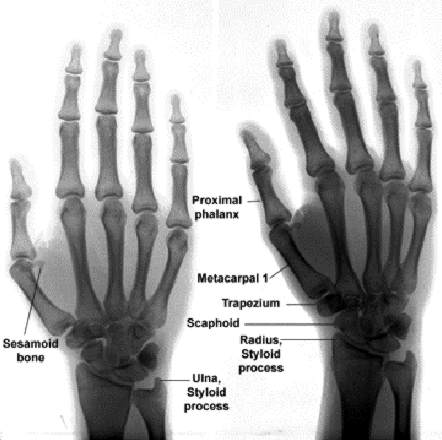

The KRush technique is best utilized in places where nerve density is high, & where deep pressure triggers endorphins (KRush Zones).  For most people, ideal locations are both the feet & hands.  The X-rays here show metacarpals & metatarsals in juxtaposition with phalanx (fingers & toes) arranged so that the 1st, 2nd & 3rd, etc phalanx on the foot X-ray correspond to the thumb, fore, middle & ring finger of the hand X-ray on the right.  On the hand, the 1st, 2nd, etc MT shown in the left X-ray, of course, correspond to carpals.  Other than semantics, hands & feet can be treated equally -- although about +66% of recipients of the technique insist that the KRush zones on the feet generate substantially more "rush". Speaking of "rush", this technique produces a literal flood of neurotransmitters within seconds after being started.  The recipient should be told in advance that they may experience a "rush" and that the entire limb being worked may feel extremely fatigued or "heavy" during the process.  The process is also extremely addictive (in the short term), which means that you should be able to give a recipient some quality time after beginning.  It is my opinion that we could reduce or eliminate much of the pain & anxiety medication prescribed if more people became aware of the KRush Technique.

The soft-tissue in & around the bones is where KRush force should be applied.  It should be very firm but never should hurt the recipient.  Again: Pain receptors should not be triggered during the process if at all possible.  A common technique is to grasp the limb with the hands of the 'KRusher' palms-down on top of the limb w. fingers wrapped around so that the tips apply even pressure between the 1st & 2nd PP, and the 4th & 5th PP (MC when dealing with the hands).  Alternate between 1st & 2nd, 2nd & 3rd; -- And 4th & 5th, & 3rd & 4th -- with respective hands.  Apply deep pressure and HOLD.  Wait 10-15 seconds & release.  Move up or down the limb slightly & repeat.  If connected to monitoring equipment, -- within 30 seconds of beginning: breathing, blood pressure & pulse should begin to drop and vasodilatation in the upper body should increase.  This is often accompanied with a "rush" feeling in the head & the onset of lethargy not unlike opiates cause.